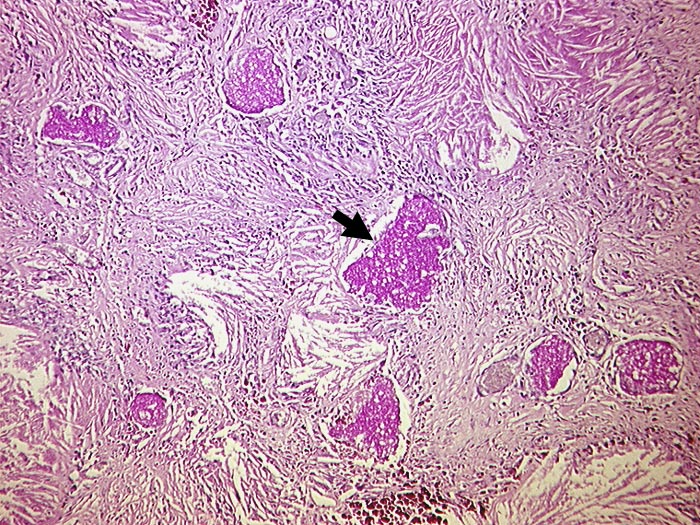

PathoPic – image database / PathoPic ID 267 - Chronische Pneumocystis jirovecii Pneumonie

Chronische Pneumocystis jirovecii Pneumonie

Vernarbung des Lungeninterstitiums mit herausgelösten Cholesterinkristallen und PAS positiven schaumigen Einschlüssen. Diese enthalten zahlreiche Erreger.

AIDS. HIV Positivität bekannt seit 2 Jahren bei iv Drogenabusus.